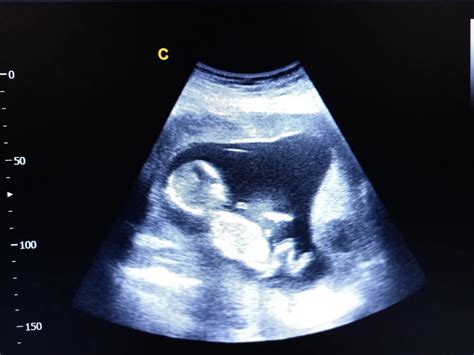

Copilul și-a definitivat dezvoltarea, iar dacă urmărești cu atenție ecografia de sarcină în săptămâna 39, vei putea observa trăsăturile acestuia. Degetele sunt deja capabile să apuce și să prindă cu putere, iar acest lucru va fi evident imediat după naștere, când micuțul îți va strânge degetul.

La 39 de săptămâni, bebelușul măsoară între 45 și 55 de cm lungime și are o greutate cuprinsă între 2,8 și 3,6 kg, fiind de mărimea unui pepene mare. Baietii pot fi ceva mai mari și mai grei decât fetele, dar nu este o regulă.